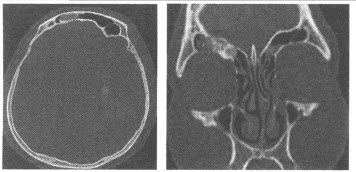

(多选题)关于动脉瘤样骨囊肿的表现描述正确的是()

C:CT及MRI上可见液-液平面